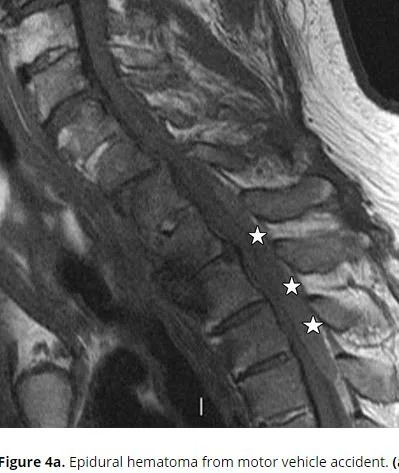

Our patient had an epidural hematoma which was unrecognized on the first visit.  Ten days later he was having difficulty moving his arms and his mother brought him back.  Review of the first CT at that time showed an epidural hematoma which had been missed.

While an epidural abscess can be seen on CT as in the case of our patient, the imaging modality of choice is the MRI.

MRI however, changes over time as hemoglobin changes its magnetic properties in various stages of evolution.  So while in the acute phase blood is hypointense on both T1 and T 2;  after ten days it will become hyperintense on both T1 and T2 signals.